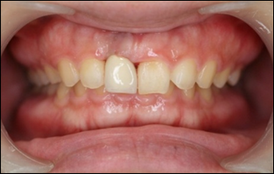

手術当日の仮歯です。

他院では歯を抜いて3か月程して、骨が回復した後にインプラントを入れる為、治療期間が半年かかると言われました。しかし当院では抜歯即時埋入という、歯を抜いて当日にインプラントを入れる治療法を行ったため3か月で治療を終える事が出来ました。

また抜歯即時埋入と同時に抜歯即時加重という、インプラントを埋入した当日から物を噛めるような歯を入れる治療法を併用したため、治療期間中、前歯部でも審美性を失わずに治療をすることができました。

完成後の口腔内写真